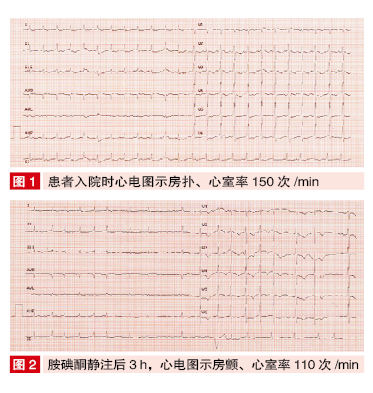

他今年36岁,心电图显示频发室性早搏,医生:都是熬夜惹的祸心电图刘医生给您讲解一位真实的病例,昨天,门诊来了一位36岁的男性患者,最近一个月来感觉心悸、心慌、胸闷,最近3天这种感觉加重了,因为看到过身边的人发生了心肌梗死,因此害怕自己也得了冠心病,来医院就诊。门诊心电图检查结果显示为:频发室性早搏。仔细询问,并无先天性心脏...